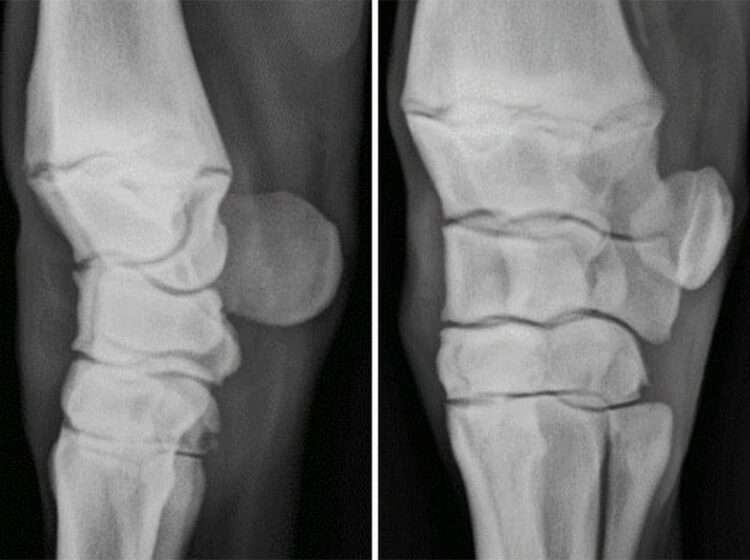

5. What is the relationship between yearling radiograph lesions and racing performance?

What’s it about?

AgriFutures Australia’s Thoroughbred Horses division is currently undertaking research to assess on a deeper level what the effects of various lesions found on x-ray can have on future race track performance. While there is literature on the topic already, there’s still disagreement between studies on what is and isn’t relevant, and much of the current research has been conducted on very different populations.

Yearling knee radiographs | Image courtesy of Tamworth Equine Veterinary Centre

This research will look at a variety of different lesions in the foot, fetlock, knee, hock, and stifle, and will be consistently graded on severity, which can then be compared to performance.

The research will also aim to assess the actual amount of lesion occurrence by analysing radiographs from over 2500 Australian yearlings.

What it means for you:

The intention is to produce a volume of research specific to the Australian Thoroughbred industry that will give buyers and vendors alike a more accurate idea of what to expect when a yearling has a lesion on x-ray, and how common it actually is for a yearling to have that lesion.